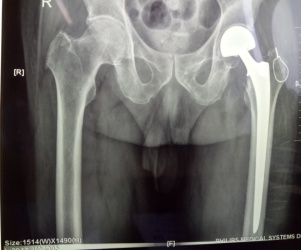

? ? ? ?7月26日,由張富軍主任主刀、張浩主治醫(yī)生協(xié)助及麻醉科龐曉宏主任及陳波副主任醫(yī)師密切配合,成功為三位高齡患者實(shí)施“人工股骨頭置換術(shù)”。

? ? ? 考慮到患者均為高齡,且合并內(nèi)科疾病,麻醉選擇硬腰聯(lián)合,第一位股骨頸骨折患者8點(diǎn)進(jìn)入手術(shù)室,血壓高至210/110mmHg,麻醉科龐曉宏主任、陳波副主任醫(yī)師緊急商討,積極處置,患者血壓穩(wěn)定在130/80mmHg左右,上午9點(diǎn)手術(shù)開始,27分鐘完成手術(shù),在患者家屬焦急等待中于10點(diǎn)整推出手術(shù)室;第二位、第三位粗隆間骨折行人工關(guān)節(jié)置換手術(shù)+骨折復(fù)位內(nèi)固定術(shù)均1小時(shí)內(nèi)完成,術(shù)后患者病情穩(wěn)定。忙碌一天的我們顧不得疲憊,晚上6點(diǎn)張富軍主任及麻醉科龐曉宏主任、陳波副主任醫(yī)師再次巡視術(shù)后患者,制定術(shù)后鎮(zhèn)痛、抗凝方案,確?;颊咂椒€(wěn)、無痛度過圍手術(shù)期。在髖、膝關(guān)節(jié)快速康復(fù)理念指導(dǎo)下,三位患者手術(shù)切口均采用美容縫合,于次日手把手指導(dǎo)患者正確下床活動方法,真正做到無痛、無管、早下地、免拆線的快速康復(fù)。目前三位患者均恢復(fù)滿意,無術(shù)后嚴(yán)重并發(fā)癥發(fā)生?;颊呒凹覍俑屑とf分,他們的笑容就是我們最大的欣慰。

患者張XX,男,75歲,6月前腦梗塞遺留左側(cè)肢體偏癱,合并高血壓、糖尿病。

患者王XX,男80歲,前列腺癌骨轉(zhuǎn)移導(dǎo)致病理性骨折,合并房顫、高血壓、冠心病。

患者馬X,男,87歲,合并糖尿病、腦梗塞。